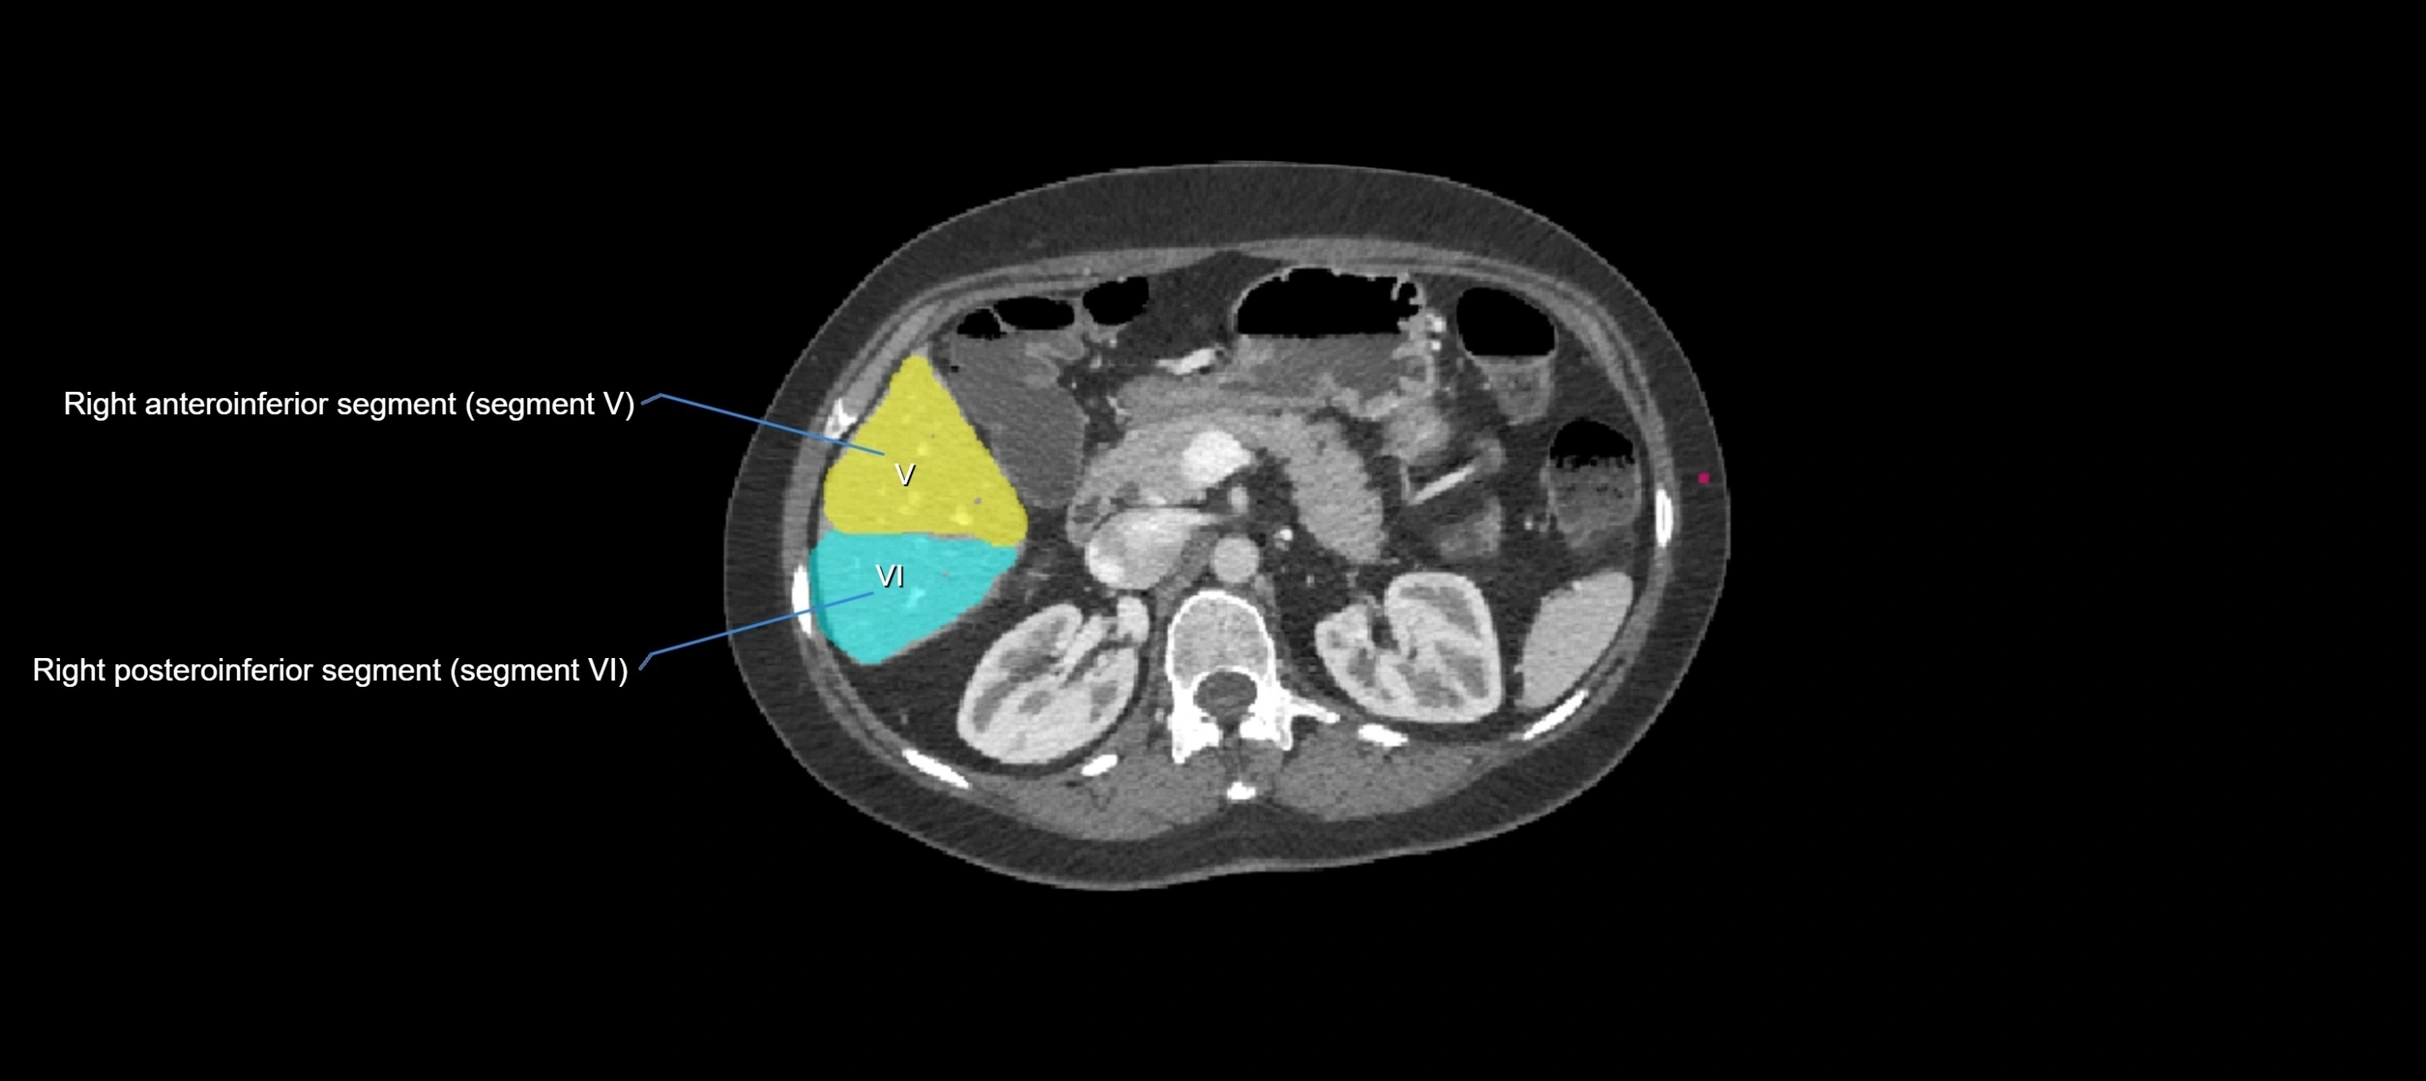

CT Image

image